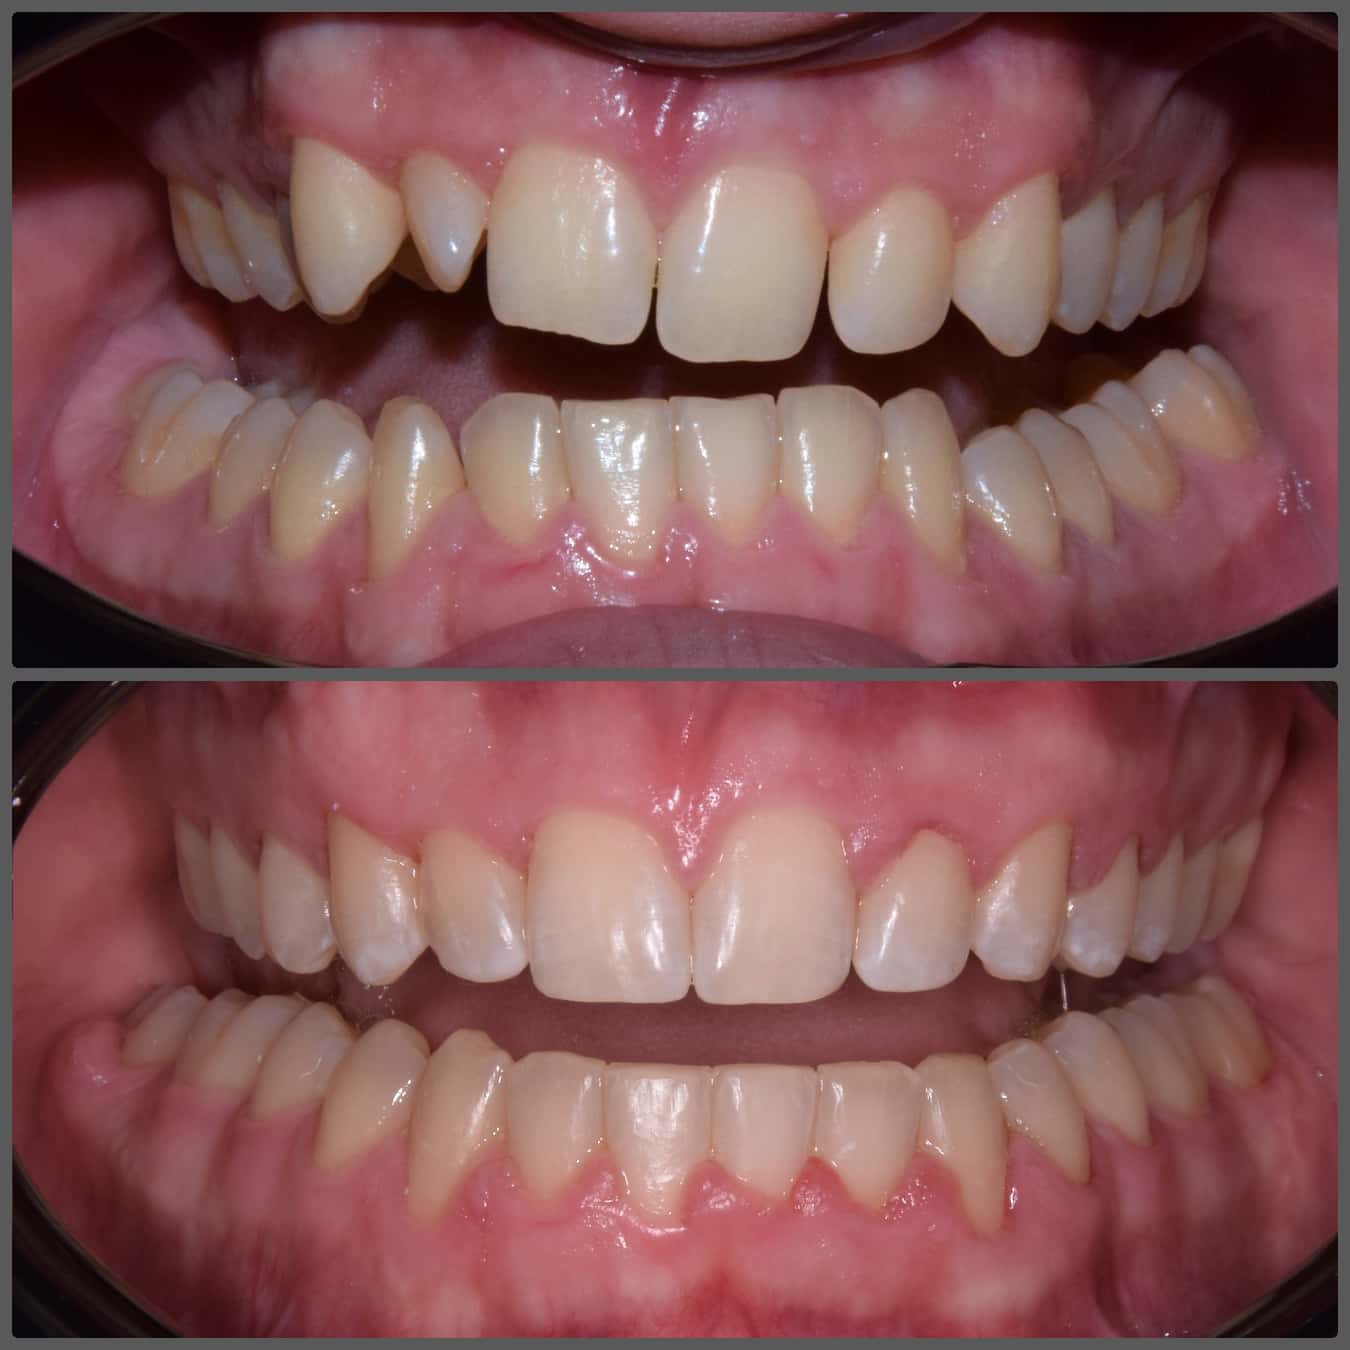

Balázs súlyos alsó torlódása miatt keresett fel magánrendelésemen. A diagnosztikus vizsgálatok során előbbin túl alsó-felső fogívszűkületet, valamint nyitott harapási hajlamot állapítottam meg. Kezelését Pitts21 alsó-felső rögzített fogszabályozó készülékkel kezdtük meg. A nyitott harapási hajlamot a hátsó fogakra helyezett harapásemelővel kontrolláltuk. A torlódott fogaknak tolórugóval és interproximális redukcióval teremtettünk helyet, és intermaxilláris gumihúzással tökéletesítettük a harapást. A fogszabályzó kezelés teljes időtartama alatt Balázs 110%-osan együttműködő volt, ezért 21 hónap alatt sikerült kiemelkedő végeredményt elérnünk.